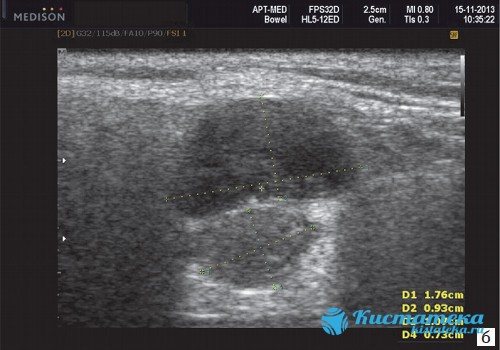

Какие параметры исследуются на ранних сроках, что видно на фото УЗИ?

Как выглядит двойня на ранних сроках? Поначалу врач видит только два темных пятнышка. Кроме того, отчетливо прослушивается биение двух сердец, видны две плаценты и два амниотических пузыря. На фото можно увидеть снимок УЗИ близнецов.

На ранних сроках при проведении УЗИ оцениваются следующие параметры плода:

- копчико-теменной размер — КТР, близнецы обычно имеют меньшие размеры, чем одиночные эмбрионы, и к 12 неделе достигают роста 6 см и массы тела 8 г;

- бипариетальный размер — БПР, расстояние между височными костями черепа;

- частота сердечных сокращений — 110-150 уд/мин;

- сформированность нервной трубки;

- наличие носовой косточки;

- толщина воротникового пространства — его расширение вместе с уменьшением носовой косточки указывает на синдром Дауна;

- сформированность внутренних органов.

Нередко на снимке УЗИ заметно, что один эмбрион меньше другого. Если расхождение невелико и составляет всего лишь несколько миллиметров, то беспокоиться не нужно, размеры выровняются или в процессе беременности, или после рождения малышей.